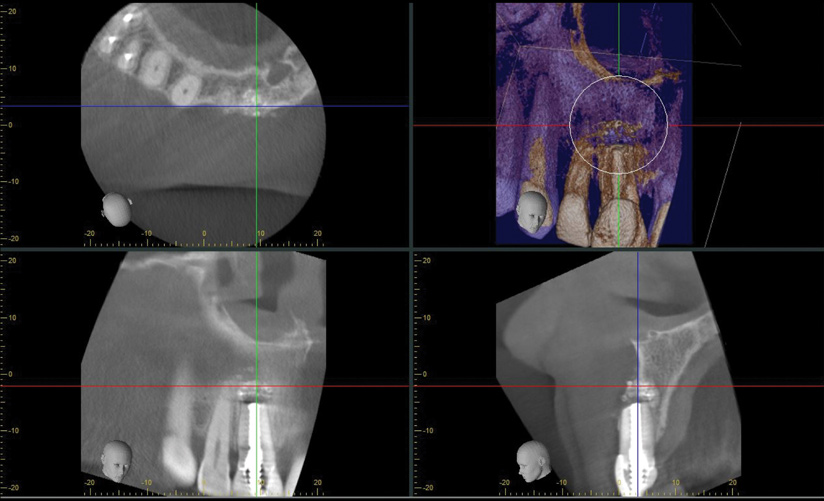

A 56-year-old female patient was referred for the evaluation of tooth No. 8 (Figure 4 and Figure 5). A periapical radiograph indicated that the tooth had undergone apicoectomy and received an excessively long post (Figure 6), and a cone-beam computed tomography (CBCT) scan of the site revealed a lack of buccal plate bone (Figure 7).

When the patient returned 4 months after the initial procedure for reevaluation, she underwent supportive periodontal therapy and was provided with detailed oral hygiene instructions (Figure 13). An intraoral scan and a postoperative CBCT scan were taken to evaluate both the horizontal and vertical hard- and soft-tissue gain. Next, implant planning software was used to merge the STL and DICOM data, which facilitated the creation of a digital wax-up (Figure 14).

The digital wax up allowed the implant position to be planned based on the ideal prosthetic position of the final restoration (Figure 14). The planned implant position adhered to the aforementioned guidelines for ideal implant placement regarding the buccal, interproximal, and apical bone, and its platform would be located 4-mm apical to the planned restorative margin. In the coronal plane, the implant was centered with the gingival zenith in a position that was located approximately 1-mm distal to the midline of the edentulous space. Following implant planning, a tooth-supported surgical guide was designed and then 3D-printed to facilitate fully guided surgical implant placement.

(7.) Pretreatment CBCT scan.

Figure 7

(14.) Three-dimensional implant treatment planning.

Figure 14

(22.) Immediate postoperative CBCT scan.

Figure 22